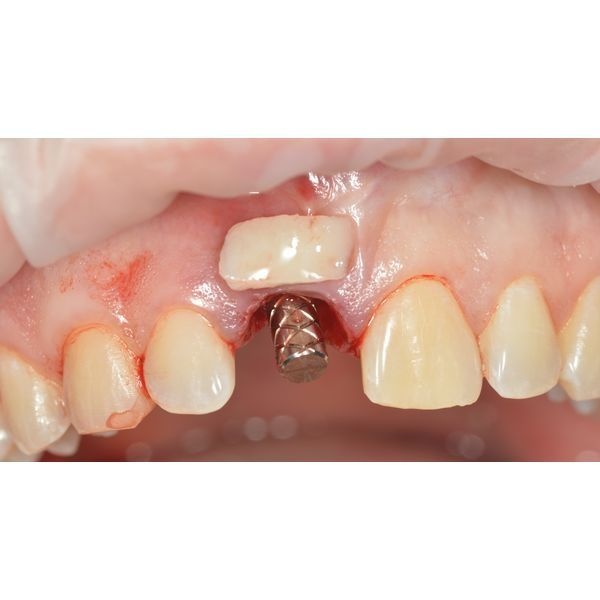

Под местной анестезией удалили зуб, после чего сформировали ложе для имплантата и провели пластику мягких тканей вокруг него. Изготовили и установили временную коронку на 4 месяца.

Через неделю после операции сняли швы. Спустя месяц провели контрольный осмотр. Протезирование запланировали примерно на 3–6-й месяц после хирургического вмешательства, точный срок зависел от приживления имплантата.

Пациент приходил на осмотр раз в месяц. Повторные КТ показывали, что имплантат приживался без осложнений.

С помощью немедленной имплантации пациенту восстановили переднюю часть зубного ряда.